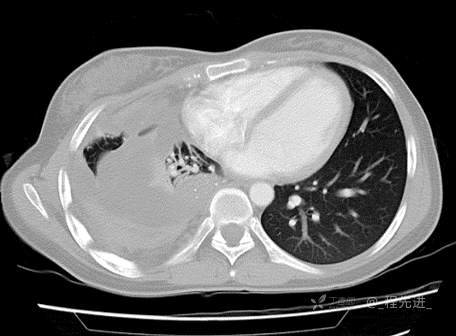

患者性别:女

患者年龄:26岁

简要病史:反复胸闷、气喘、咳嗽半年